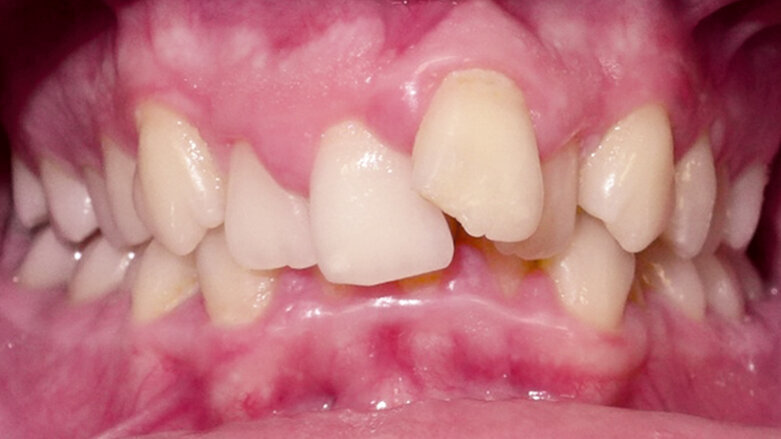

17letý chlapec přišel na konzultaci v prosinci 2014. Při intraorálním vyšetření bylo zjištěno: vztah molárů v I. třídě dle Anglea oboustranně a vztah špičáků v I. třídě vlevo a II. třídě vpravo. Šířka horního zubního oblouku v úrovni molárů byla normální, v místě premolárů však byl zubní oblouk výrazně zúžený a v mezišpičákové oblasti bylo výrazné stěsnání. V dolním zubním oblouku (úzký, tvar paraboly) bylo stěsnání s úplným deficitem místa pro zub 42, který byl v ektopické lingvální poloze. Hloubka skusu byla stoprocentní s traumatickým nákusem do gingivy v okolí dolních frontálních zubů. Zuby horního oblouku byly mírně větší než průměr, s malým nepoměrem Boltonova indexu. Objektivní extraorální vyšetření odhalilo syndrom dlouhého obličeje, vývoj střední třetiny obličeje byl normální a nazální pyramida byla široká ve spojení s mírnou mandibulární retruzí (obr. 1a–h).